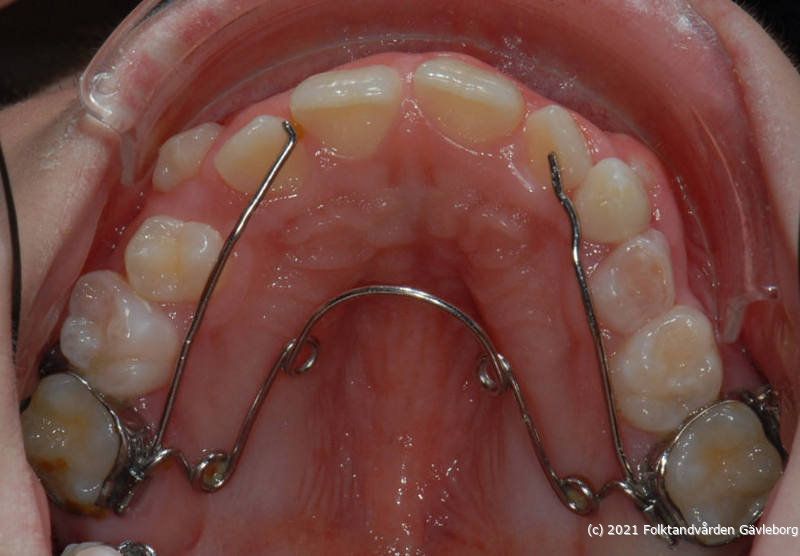

På ortodontiklinikerna diagnostiserar och behandlar vi bettfel på både barn och vuxna. Alla våra patienter kommer på remiss till oss. Vi behandlar bettfelen med fastsittande och avtagbar apparatur. Hos oss behandlas också de patienter som har avvikelser i käk- och ansiktsskelettet och som kräver tandreglering inför rekonstruktiv kirurgi. Vi har ett nära samarbete med allmäntandvård, privattandvård och övrig specialisttandvård i länet samt ett gott samarbete med Akademiska Sjukhuset i Uppsala när det gäller barn med olika syndrom och läpp-käk-gomdefekter. Våra specialistkliniker finns i Gävle och Hudiksvall.

Här nedan hittar du några exempel på vanligt förkommande behandlingar. Hittar du inget som passar det du vill visa, gå in på menyn ovan genom att föra musen över "Information". Navigera sedan till respektive apparatur. Klickar du på rubriken "Visa alla bilder" får du upp samtliga apparaturer som finns här.